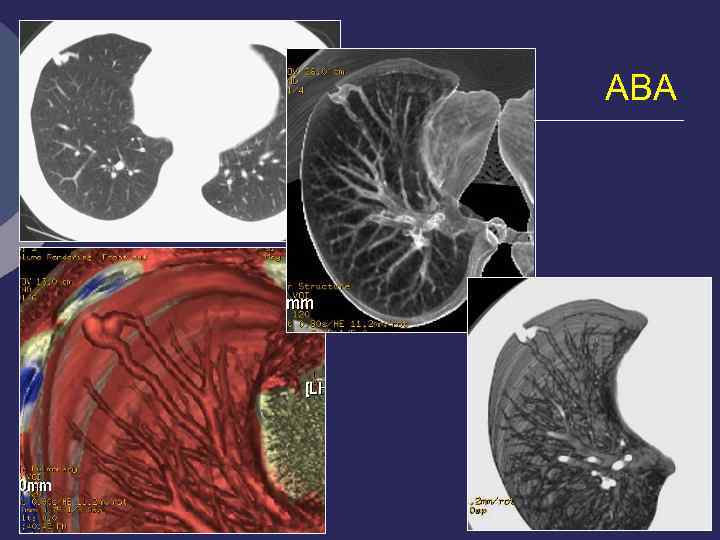

Внутрилегочная секвестрация

Аномальный сосуд, отходящий от аорты ЧС ВБА КТ-АГ. 3 D объемная МР-АГ реконструкция

Легочная секвестрация Аномальный сосуд, отходящий от Ао выше диафрагмы

МР-ангиография. Внутрилегочная секвестрация

Легочная секвестрация (Pryce, 1946). Ø Порок развития, характеризующийся наличием участка легочной ткани, расположенного внутри легкого или вне его, не связанного с бронхиальной системой легкого, содержащего элементы бронхиальной и альвеолярной ткани Ø Кровоснабжение - аномальная артерия, отходящей от Ао или ее ветвей Ø Отток - в непарную или полую вену Ø 3 -6 неделя эмбриогенеза Ø 1% оперированных по поводу хроничес- ких нагноений легких

Rg-диагностика секвестрации Ø Все признаки кисты (заполненной или вскрывшейся) Ø Локализация: 80% - 10 сегмент, 12% - 10+6 сегменты 6% - 6 сегмент. , 1 -2% - средняя и верхняя доли Ø Аортография – дополнительный сосуд, отходящий от аорты или ее ветвей к кисте, обычно проходит в толще легочной связки Ø Дифференциальная диагностика: абсцесс, бронхоальвеолярная киста, новообразование, туберкулез